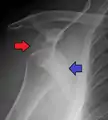

A diagnosis of shoulder dislocation is often suspected based on the person's history and physical examination. Radiographs are made to confirm the diagnosis. Most dislocations are apparent on radiographs showing incongruence of the glenohumeral joint. Posterior dislocations may be hard to detect on standard AP radiographs, but are more readily detected on other views. After reduction, radiographs are usually repeated to confirm successful reduction and to detect bone damage. After repeated shoulder dislocations, an MRI scan may be used to assess soft tissue damage. In regards to recurrent dislocations, the apprehension test (anterior instability) and sulcus sign (inferior instability) are useful methods for determining predisposition to future dislocation.

A Hill–Sachs lesion is an impaction of the head of the humerus left by the glenoid rim during dislocation.[6] Hill-Sachs deformities occur in 35–40% of anterior dislocations. They can be seen on a front-facing X-ray when the arm is in internal rotation.[9] Bankart lesions are disruptions of the glenoid labrum with or without an avulsion of bone fragment.